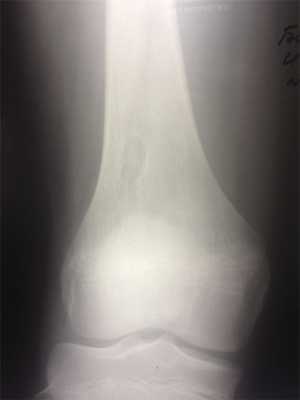

При рентгенологическом исследовании МФД выглядит как округлое или овальной формы литическое образование кортикального слоя (или субпериостально), чаще немного вытянутое параллельно оси кости. Границы четкие, как правило, хорошо заметна небольшая зона остеосклероза вокруг (рис. 3). По мере роста МФД начинает распространяться в медуллярном направлении. Поэтому НОФ всегда выглядит эксцентрично, но также с четкими границами и зоной перифокальных остеосклеротических изменений (рис. 4). При больших поражениях, занимающих более трети—половины поперечника кости, часто можно обнаружить дольчатость за счет склерозированных септ, в составе которых при гистологическом исследовании определяется фиброзная ткань с очагами реактивного остеогенеза. В данных случаях заболевание может манифестировать патологическим переломом. В редких случаях контуры НОФ могут выходить за анатомические пределы кости. Периостальная реакция в большинстве случаев отсутствует.

Рис. 3. Хорошо ограниченный кортикальный очаг поражения в зоне дистального метафиза бедренной кости. Перифокальные склеротические изменения не выражены. Стадия, А по Ritschl.

Рис. 4. Хорошо ограниченный очаг поражения дистального метафиза большеберцовой кости с выраженным перифокальным склерозом, больше выраженным в области диафизарного полюса образования. Стадия D по Ritschl.

P. Ritschl и соавт. [6] описали процесс эволюции МФД и НОФ от их возникновения до полного склерозирования, основываясь на рентгенологических данных и выделили 4 стадии: A, B, C и D. Стадия A: небольшой кортикальный округлый или овальный эксцентричный очаг расположен вблизи зоны роста (близко к эпифизу). Зона перифокального склероза практически отсутствует. Стадия B: очаг поражения дистанцируется от эпифиза, приобретает неправильные поликистозные очертания, появляется тонкий склеротический ободок по периферии. Стадия C: склеротические изменения становятся выраженными, причем начинаются, как правило, с диафизарного полюса образования. Стадия D: образование полностью замещается гомогенной зоной склеротических изменений. Затем МФД/НОФ замещаются нормальной костной тканью и не выявляются рентгенологически. Активный рост МФД и НОФ происходит на стадиях A и B, при выявлении образования в стадиях B и C увеличения в размерах в динамике не наблюдалось.